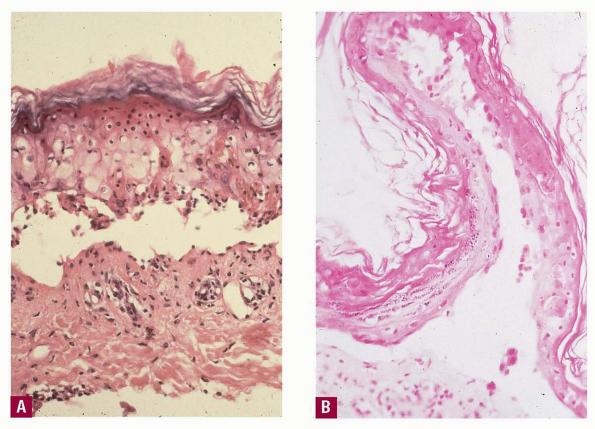

Toxic epidermal necrolysis = انحلال البشرة النخري السمي